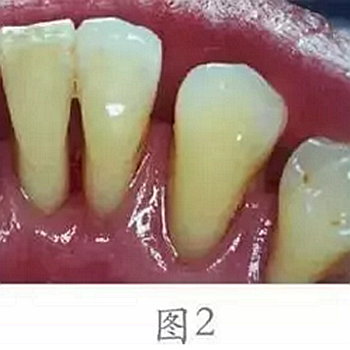

還有一些是因為不太理想的假牙或者補的牙有一些不光滑的地方導致經(jīng)常有食物嵌塞,這些都極易導致細菌聚集而刺激牙齦,發(fā)生炎癥性出血。